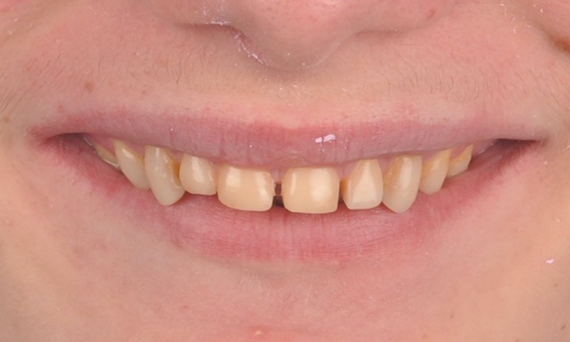

A particular and protracted case of skeletal Class II malocclusion and generalized amelogenesis imperfecta in a teenager was referred for prosthetic rehabilitation. The aim of the treatment was to prepare the remaining tooth structure, remove undercuts, and make room for all-ceramic crowns covering the entire dentine and simulating the lost enamel.

Before: Initial situation prior to orthodontic treatment.

After: Final result, 1 week post-operative.